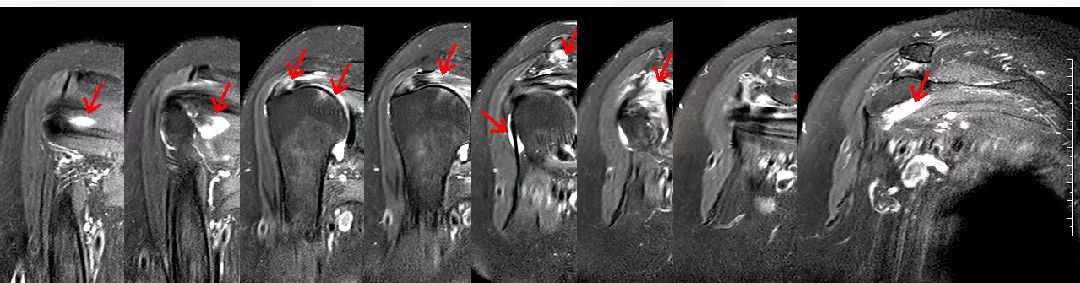

根据患者的发病特点,我们给出入院诊断:一、肩周炎?二、肩袖损伤?三、2型糖尿病。当然,我们还要与可能引起肩关节疼痛的其他疾病相鉴别,如肩关节肿瘤、肩关节感染、颈椎病、冠心病、肺或胸膜病变。 患者入院后,我们为患者安排相关的医学检查,以明确诊断。肩关节感染和肿瘤可以引起肩关节疼痛和活动受限。患者的血常规检查、肝功能检查、肾功能检查、肿瘤标志物筛查结果都是正常的,空腹血糖17毫摩尔/升,糖化血红蛋白9.8%。从检查结果可以看出,该患者血糖控制不佳,与其自述的血糖控制尚可明显不符。患者的血沉、C反应蛋白、血常规等检查结果都是正常的,只有降钙素原稍微高一点儿,没有特殊意义,所以对该患者可以基本排除肩关节感染和肿瘤。 一些心脏病可能不表现为心前区疼痛,反而是放射至肩关节位置的疼痛,所以有肩关节疼痛时,患者一定要警惕心脏病的可能。该患者的心电图和心脏彩超检查结果都没有大问题,所以心脏病可以基本排除。 靠近左肩部的肺或者胸膜的病变也可以导致肩关节疼痛。该患者的胸部CT检查结果显示双下肺轻度炎症,未见肿瘤病变,所以肿瘤、肺或胸膜病变也基本排除。 与肩周炎和肩袖损伤最易混淆的疾病通常是神经根型颈椎病,颈椎的颈4、颈5神经支配的是肩关节,如果颈椎病压迫颈4、颈5神经根,就会引起肩关节疼痛。很多肩关节疼痛的颈椎病患者一开始会被误诊为肩周炎。对该患者,我们让其做了颈椎磁共振检查,结果未见明显异常,颈4、颈5神经根未见受压,所以颈椎病也基本排除。 肩关节疼痛最主要的检查是肩关节磁共振。从这个患者的肩关节磁共振检查报告,可以见到肩胛下肌、冈上肌、冈下肌、小圆肌、肱二头肌长头腱、喙突下滑囊、肩关节腔、肩峰下滑囊等结构中有大量的炎症信号、水肿甚至积液,并且冈上肌可见部分撕裂,所以对这个患者的肩周炎和肩袖损伤诊断都是成立的。 至此,对该患者的初步诊断明确:一、肩周炎;二、肩袖损伤;三、2型糖尿病。诊断明确后,对下一步的治疗才好确定方案。